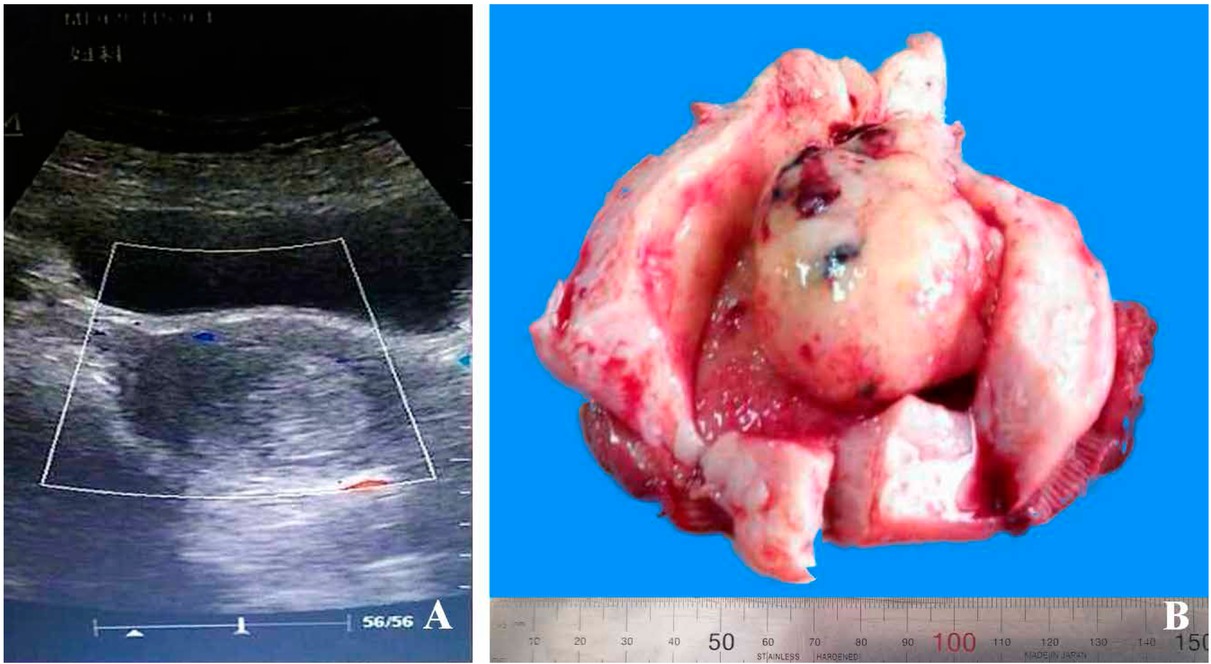

A 65-years-old female, gravida 2 para 2, was admitted with abnormal vaginal bleeding that had continued for 2 months. A pelvic ultrasound showed that the uterine cavity was occupied by an 7.0×4.5 cm oval shaped mass; there was vascularization [Fig. 1A] but extensive examination for metastases that included a chest X-ray and thoracic computerized tomography (CT) showed no abnormalities. Biochemical examination revealed that tumor markers CA-125, CA-199, and CEA were all within normal range. However, her serum alpha fetoprotein (AFP) was elevated, at 359 ng/ml. Cytology of the cervix was negative for intraepithelial lesion or malignancy (NILM). The patient had a one-year history of diabetes that was being treated with metformin. Judged from those clinical features and imaging findings, a gynecologist concluded that it was likely that endometrial cancer was present. Therefore, curettage of endometrium was performed immediately. However, the pathological analysis revealed only a small amount of endometrial atrophy because of limited tissue samples. Then, total hysterectomy and bilateral salpingo-oophorectomy were performed.

Imaging and gross feature of the case. A) Ultrasound images showing that the uterine cavity was occupied by an oval shaped mass. B) The gross appearance of the brown polypoid tumor located in the uterine cavity and originated from the endometrium.

The removed uterus measured 12.0×8.0×5.5 cm and weighed 185 g. Sectioning revealed that the depth of the uterine cavity was 10 cm, in which a brown polypoid tumor 7 cm in diameter was found. The tumor originated from the endometrium and extended into the myometrium; the depth of the invasion was 0.2 cm and the total myometrial thickness was 2.0 cm. The tumor was well circumscribed but non-encapsulated, with a brown soft cut surface and large areas of hemorrhage and necrosis. No hair and teeth were present. The thickness of the rest of the endometrium was 0.1 cm [Fig. 1B]. The appearance of the cervix was normal, with length 2 cm and diameter of 2.5 cm. The uterine serosa, bilateral ovaries and fallopian tubes, abdominal and pelvic wall and omentum had no unusual features.